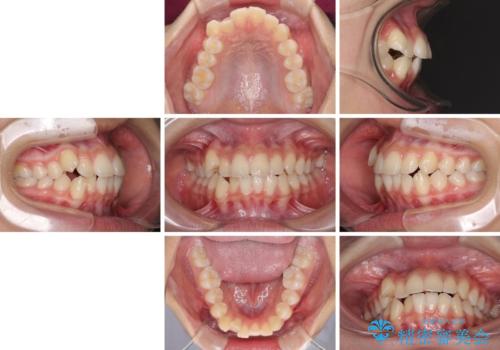

- 前歯のデコボコと八重歯を気にして来院された患者様です。

本人はあまり実感はありませんでしたが、同席されたご家族より口がすぐに開いてしまうことを指摘されていました。

口元に力の入る歯列であったため、上顎左右第一小臼歯4本を抜歯するワイヤー矯正を行うこととしました。